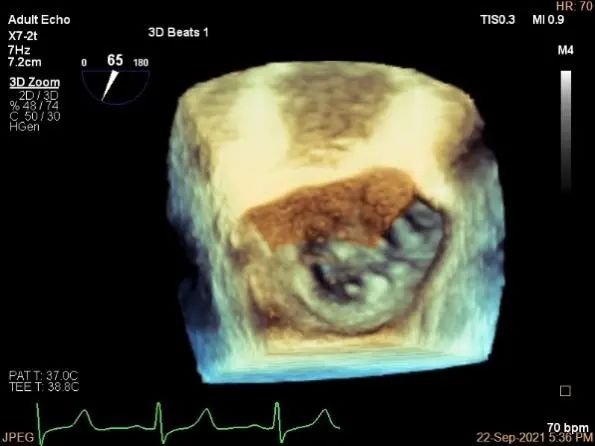

三维评估两个夹子位置

3D-color再次确定未见残余分流

评估瓣口条件,平均跨瓣压差:4mmHg